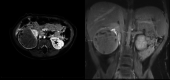

Figure 1

Figure 1. MRI revealing well-defined, predominantly solid hypoenhancing right renal mass with a small cystic area in the periphery of the lesion